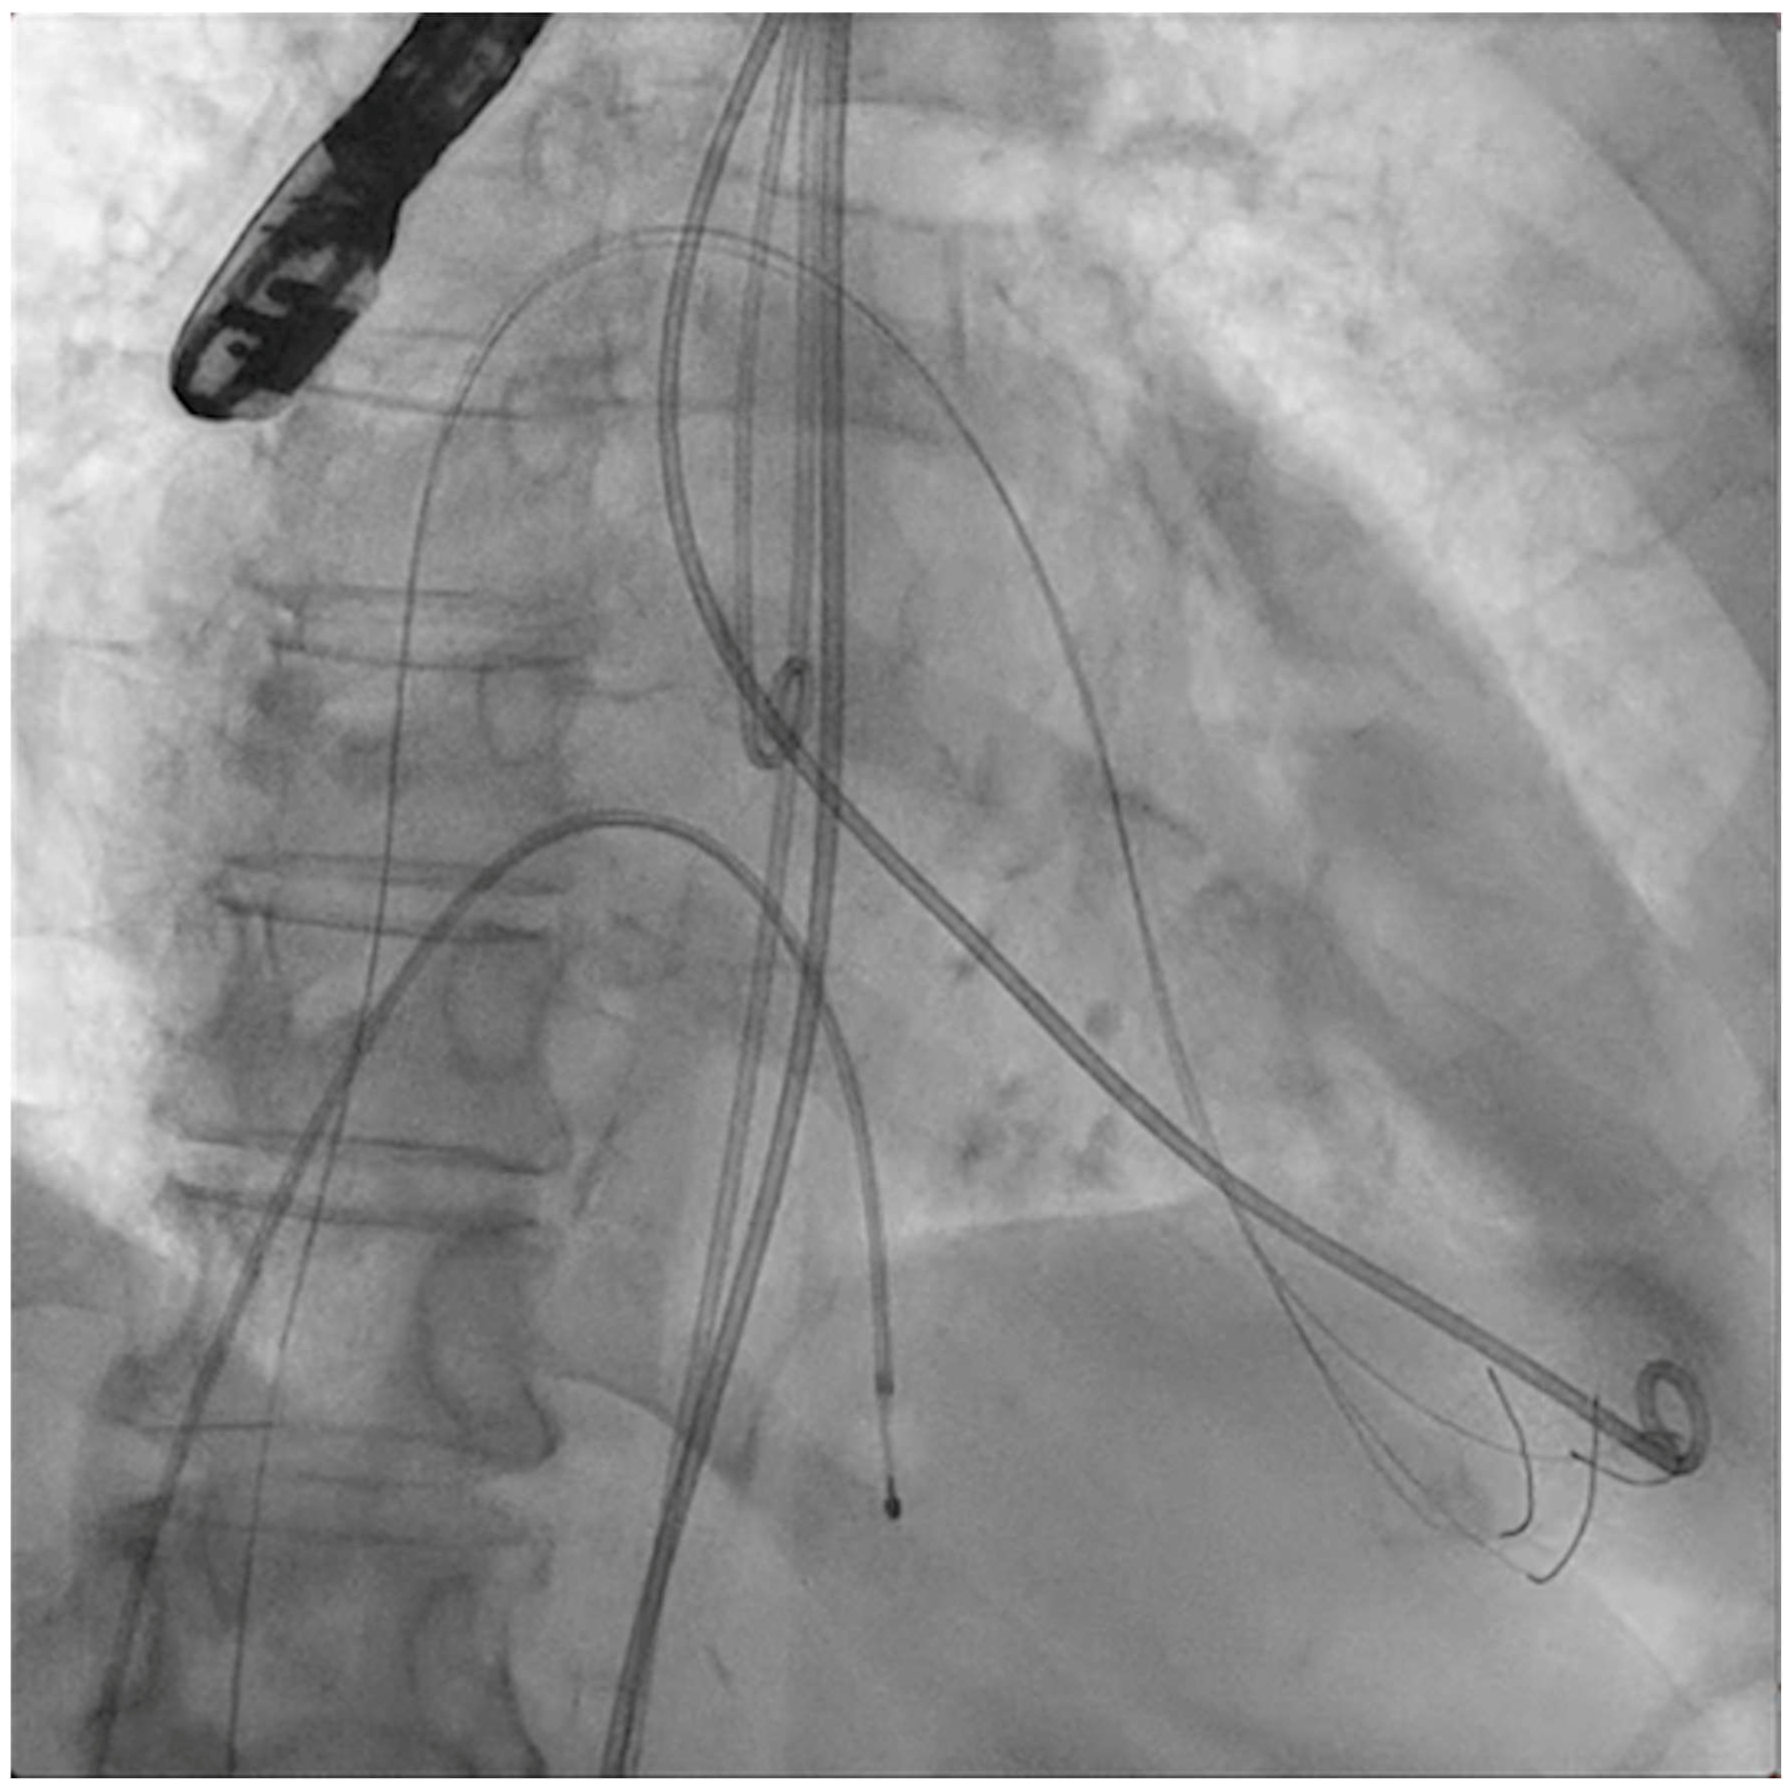

The next steps consist of crossing the mitral valve with three long high-support 0.014´´ wires downstream into the left ventricle (LV) (Figure 2) and then advancing three lithotripsy balloons (Shockwave Medical) across the mitral valve; with rapid pacing (120 beats/min), simultaneous inflations of all balloons will deliver a total of 90 pulses from each balloon (Figure 3). Finally, access to the LV has to be attained again with the Safari wire to complete PMC with large balloons appropriately sized to the mitral valve area and diameters (Figure 4). Embolic protection devices are encouraged to avoid neurological or systemic ischemic events due to calcific debris.

Figure 3.

Simultaneous inflation of three 7 × 60 mm shockwave balloons on the mitral valve for lithotripsy applications.